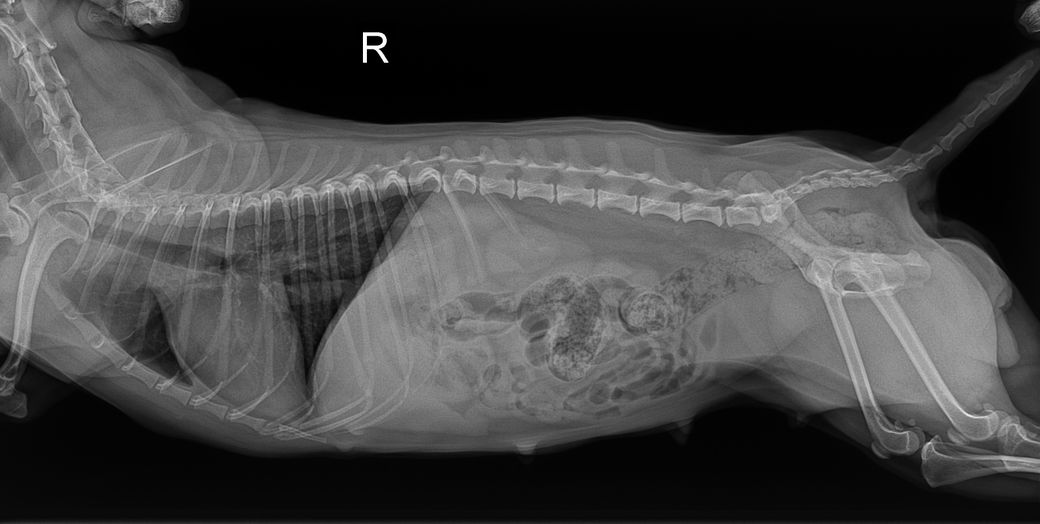

8살 암컷 강아지이고 어제 유선종양이랑 중성화 수술했는데 수술 전에 찍은 엑스레이에서 궁금한 점이 생겨 물어봅니다 혹시 엑스레이 상에서 제가 빨간색으로 동그라미 친 부분이 뭔 지 알 수 있을까요? 정확하게능 아니더라도 가늠이라던지 한번만 봐주세요..

복배상에서는 무기질 밀도로 보이지만 외측사에서는 동일한 밀도의 구조체가 보이지 않고, 해당 위치 수준으로 유두 즉, 젖꼭지가 외측상에서 대형으로 관찰되어 젖꼭지가 복배상에서 겹쳐 강조된 상태로 보입니다.

즉, 젖꼭지입니다.

• 외측상에서는 대변 때문에 가려져서 잘 보이지 않지만, 복배상에서는 원형으로 보이는듯 합니다.

일차적으로 배속에 있는 대변이 어느정도 다 빠진 후 다신 방사선 촬영하시는 것을 권유드립니다.